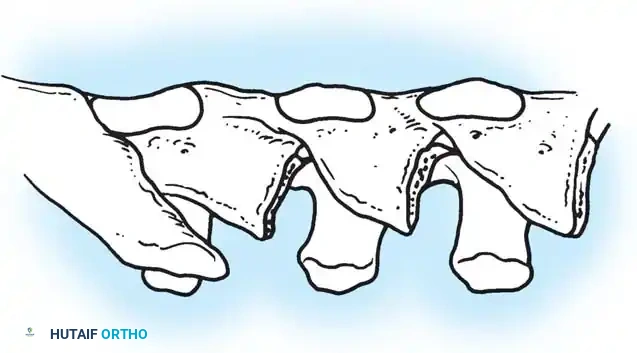

The Moe Technique (Thoracic Spine)

The Moe technique is a highly effective method for achieving intra-articular arthrodesis in the coronally oriented thoracic facet joints.

Fig. 38-26: The Moe technique of thoracic facet fusion, demonstrating the creation of hinged bone flaps.

- Expose the spine fully to the tips of the transverse processes.

- Using a sharp osteotome or Cobb gouge, begin a cut over the cephalad articular process at the base of the lamina.

- Carry this cut along the transverse process almost to its tip. Bend this cortical fragment laterally so it lies between the transverse processes, ideally leaving it hinged on its lateral periosteal attachment to preserve local vascularity.

- Thoroughly denude all articular cartilage from the superior articular process using a sharp curet.

- Make a secondary cut in the superior articular facet, working medially to laterally, producing another hinged fragment.

- Pack the resulting intra-articular defect tightly with cancellous bone graft.